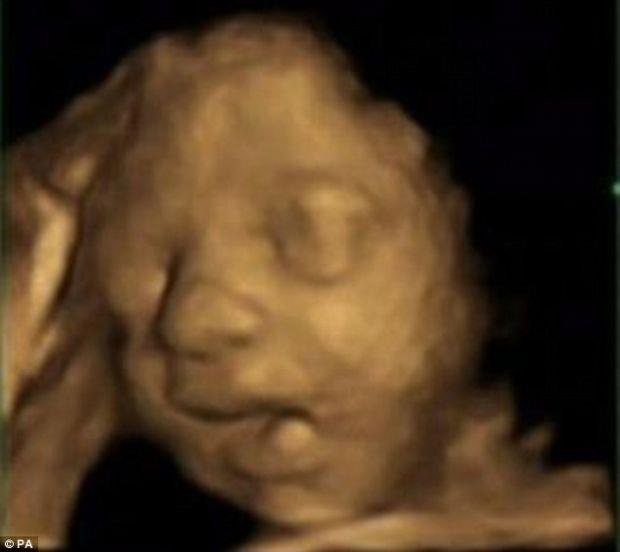

Bebeğin esneme anı

Bebeğin esneme anı galerisi resim 4